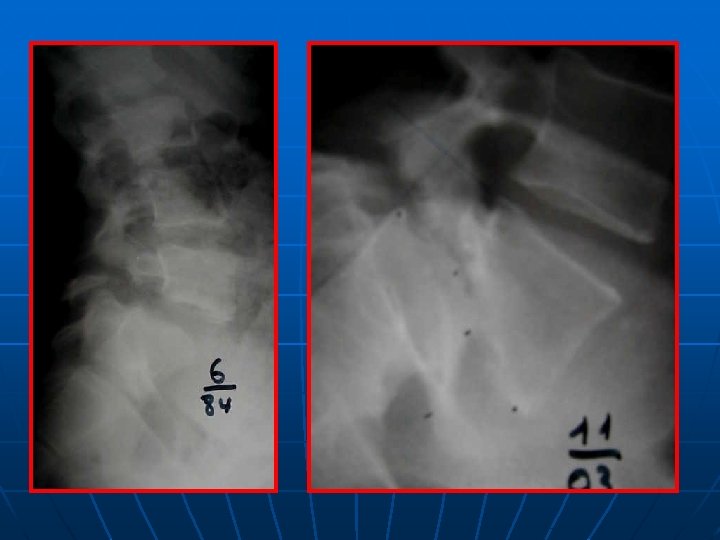

SPONDYLOLESTHESIS ISTHMIQUE Rx standard: face+profil+3/4 D-G Découverte au stade de déplacement n Lombalgies isolées: pas d’autres explorations n Lombosciatiques: Rx dynamiques+ grand format+IRM ( TDM peu d’apport) n

52 ans, spondylo L 5 -S 1 grade I, Beaujon 10

+18 mois, Beaujon 80%